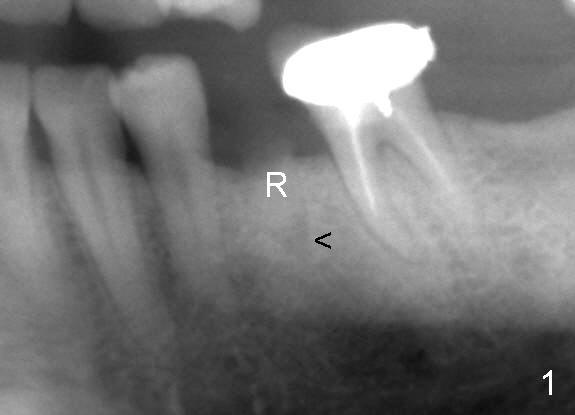

A 44-year-old lady has poor dentition. The tooth #20 has a residual root (Fig.1 R). Immediately after extraction, osteotomy is formed by drills (Fig.2: 3.5x17 mm); a 4.5x17 mm implant is placed (Fig.3 (arrowheads: boundary of the socket)). The patient returns 9 months later with increased radiolucency around the implant (Fig.4) and buccal swelling (Fig.5, asymptomatic). Raising the buccal flap confirms bone loss around the implant (Fig.6). Following debridement, allograft is placed. The source of the infection is unknown.